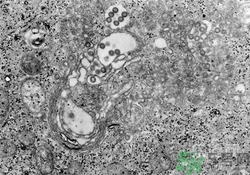

裂谷熱病怎么治?裂谷熱病的癥狀有哪些?

裂谷熱病怎么治療

本病無特效藥物治療,大多數(shù)RVF為輕癥病例且病程較短,無需特別治療,對(duì)重癥病例主要是對(duì)癥和支持治療。

抗病毒治療

利巴韋林在動(dòng)物實(shí)驗(yàn)和細(xì)胞培養(yǎng)中有抗RVFV作用,可考慮在早期試用。